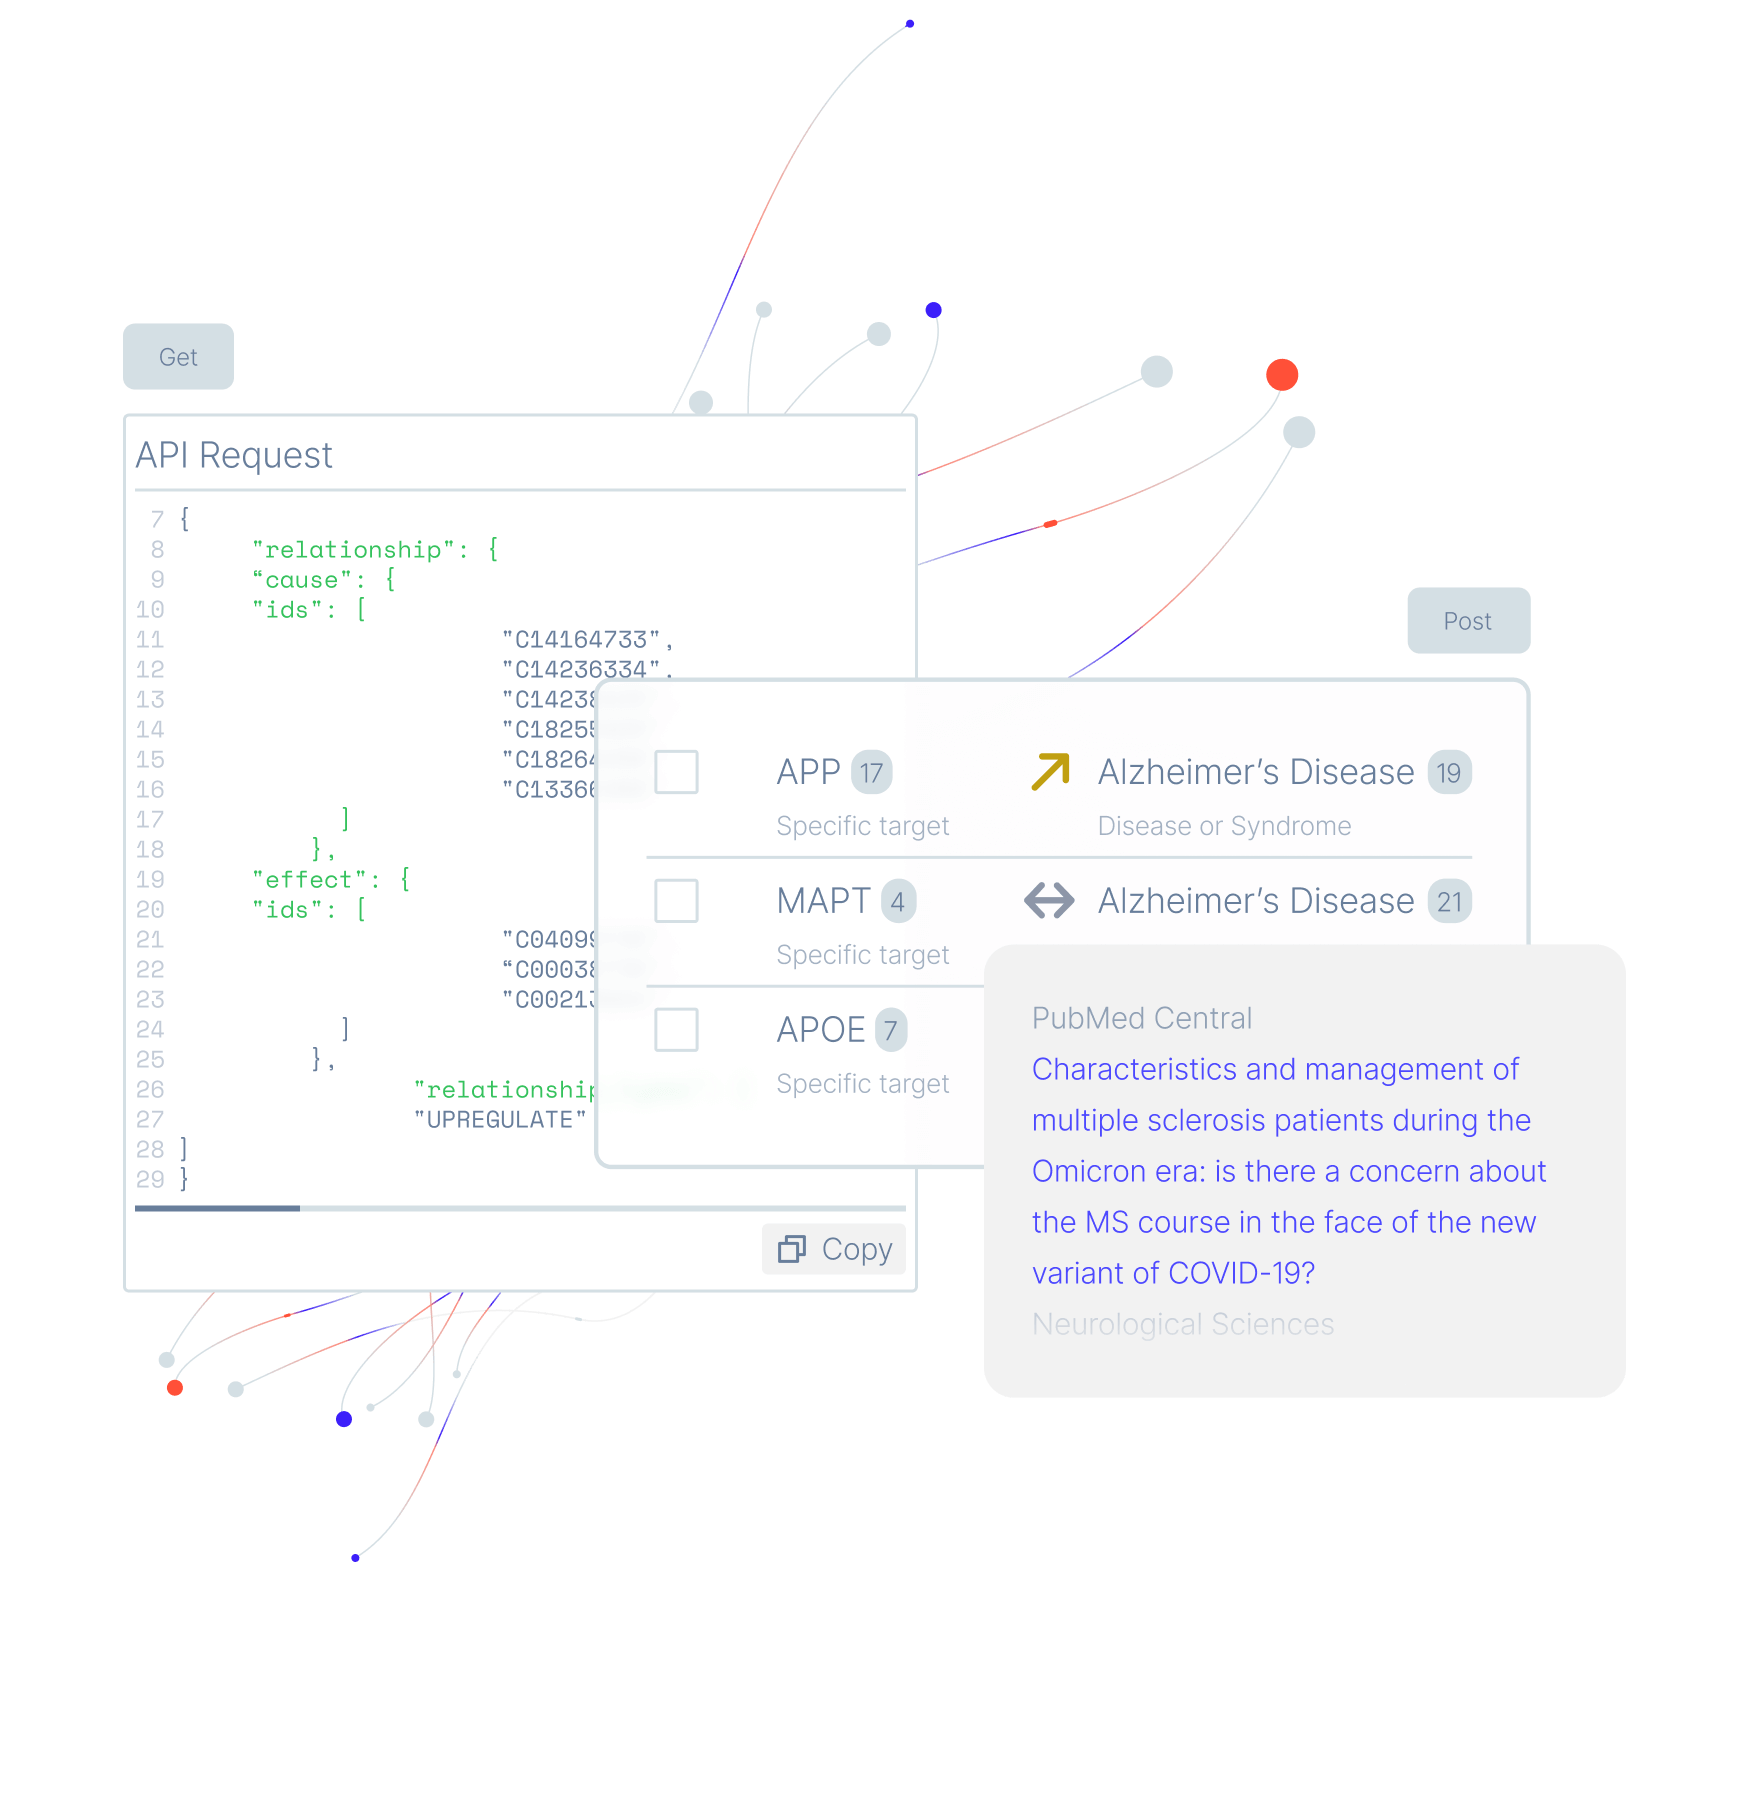

Cut through the noise with the largest and most precise knowledge graph on the market. Sort through millions of data points in minutes and get information about directionality that is absent from other knowledge graphs.

Learn moreBring the most powerful life sciences knowledge graph in-house

Run rigorous and robust analyses by querying the knowledge graph with 500 million relationships. Empower your bioinformaticians and data scientists to be a stronger partner to scientists and increase program success rates with data that is much more complete and reliable.

Take control and move at top speed with an AI platform, APIs, and

customizations for maximum efficiency, security, and flexibility.